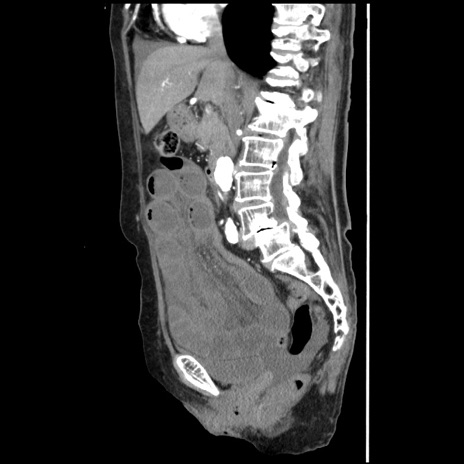

症例1(矢状断像)

【症例】80歳代女性

【主訴】腹痛

【現病歴】8時間前から腹痛あり来院。

【既往歴】糖尿病、脂質異常症、子宮体癌にて子宮全摘術

【身体所見】意識清明・会話良好だが腹痛で苦悶様、全腹部にわたって反跳痛と圧痛あり

【データ】WBC 13600、CRP 0.14、LDH 224、CK 90